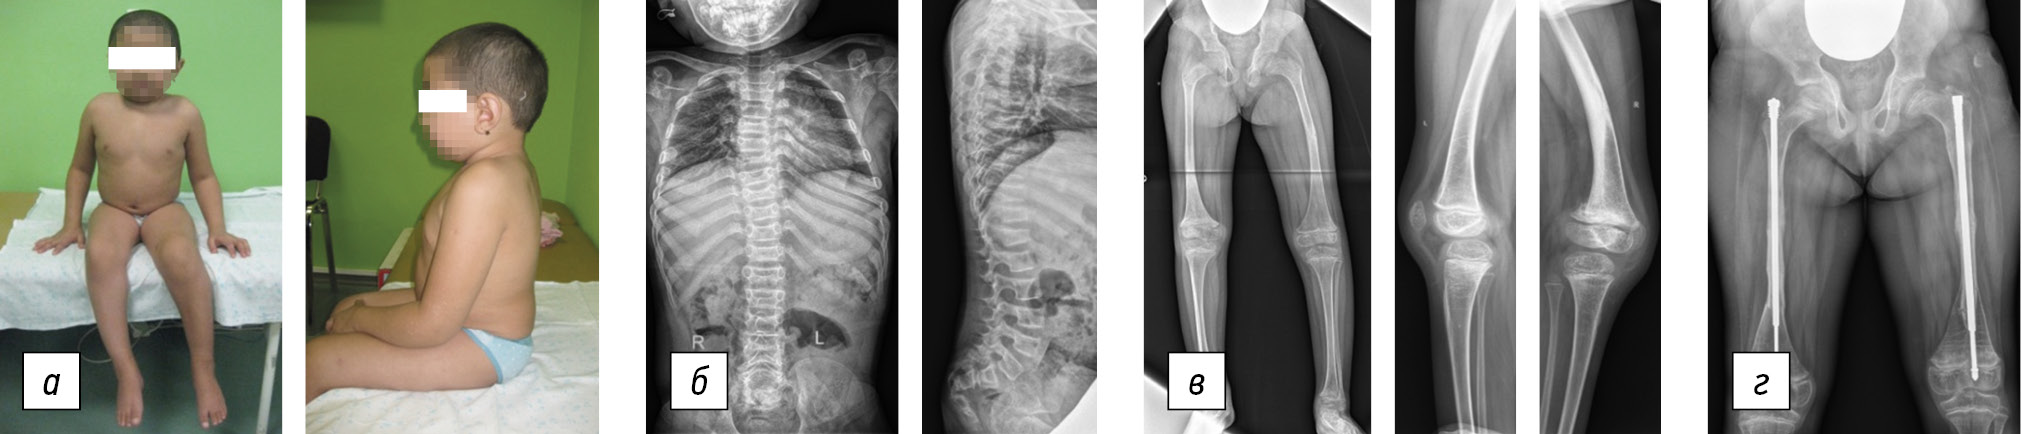

Clinical case 2

Patient I, delivered independently during the third term of his mother’s third pregnancy, had a birth weight of 2700 g and a height of 51 cm. At birth, patient I had flexion contractures of the elbow and knee joints at a 90° angle, ulnar and hamstring skin pterygium, equino-valgus deformities of the feet, skin pulling in the knee joint area, protruding frontal tubercles, and plagiocephaly. At age 1, he underwent stage plastering of the feet, achillotomy, and orthotization. At age 2, the patient underwent posterior medial release on both the right and left feet. Simultaneously, stage plastering was performed to eliminate flexion contractures of the elbow joints. Before treatment, the extensor deficit was 60° on both sides. Following treatment, it decreased to 30°. At age 3, to eliminate flexion contractures of the knee joints, lengthening of the tibial flexors on both sides was performed, followed by correction with plaster casts. The knee joint extensibility deficit before surgery was 70°; however, it completely improved after treatment. The child experienced recurrent flexion contractures in the elbow and knee joints during growth, which required repeated correction with staged plastering and subsequent orthotization. After the elimination of knee joint contractures, the boy was able to walk with assistance within the house. However, he lost this ability after relapse. At age 3, he experienced a fracture in the upper third of his left femur for the first time. Examination revealed a decrease in bone mineral density (Fig. 3). Bisphosphonates were administered parenterally twice a year from age four to the present to treat osteoporosis, resulting in a decrease in fractures. At age 5, corrective osteotomy of the right and left femur at two levels was performed to correct femoral bone deformity, followed by fixation with a telescopic rod. Standard consolidation periods were observed.

Fig. 3. Patient I, 4 years old, Bruck syndrome, type 2: a, general view of the patient; b, spine radiographs in anteroposterior and lateral projections: 45° kyphosis, decreased height, and wedge-shaped vertebrae; c, panoramic radiographs of the lower extremities in anteroposterior and lateral projections: varus-antecurvation deformity of the femur bones